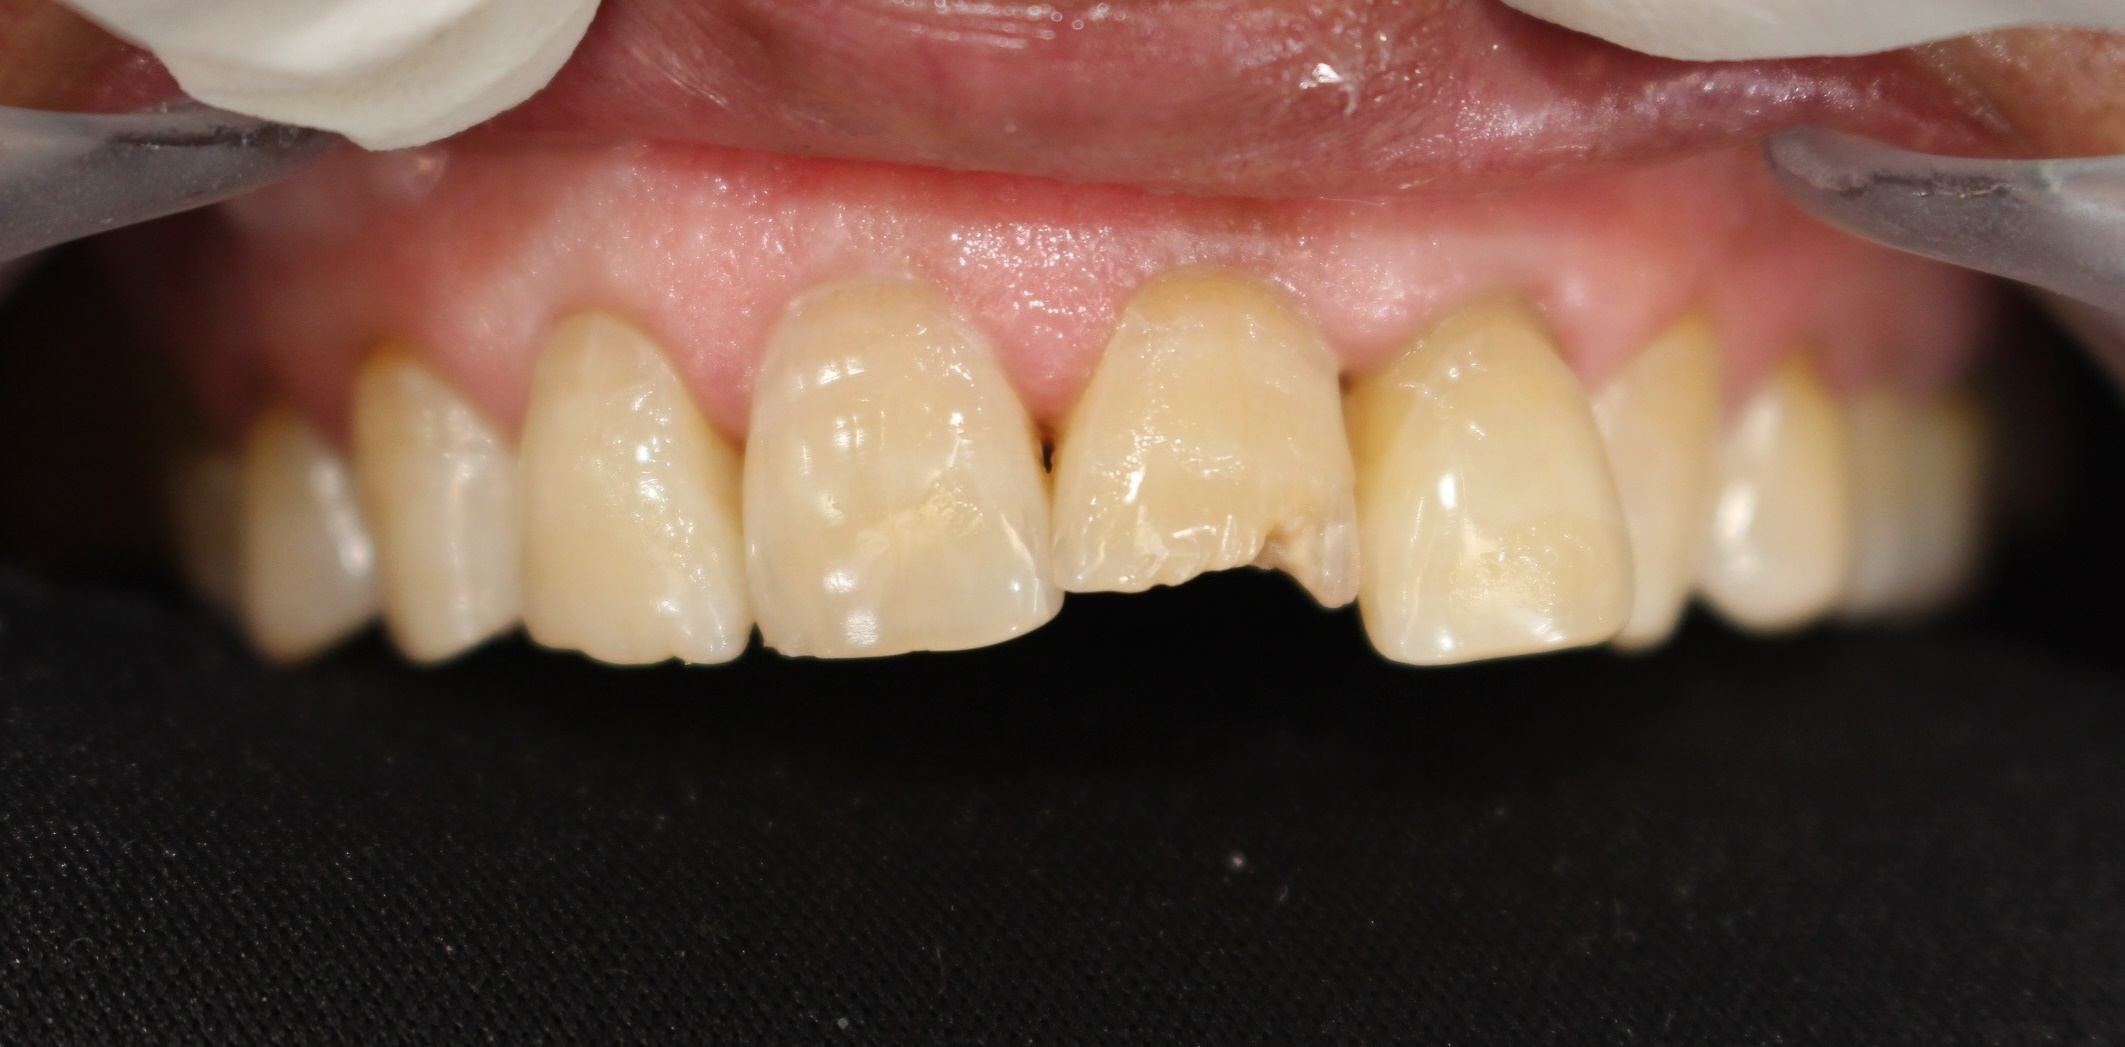

수술 전

수술 후

전치부절단면레진

전후사진